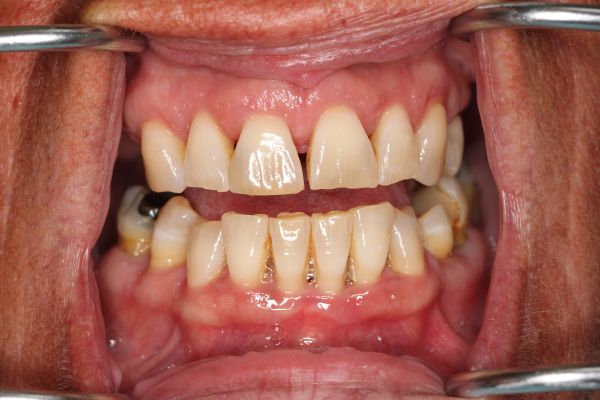

Crowns on upper front teeth 6-11 and lower front teeth 22-27 Crowns on the molars and bicuspids on the upper right and lower right. 3/4/5/28/29/30.

It’s never too late to restore and rejuvenate your smiles. After years of hiding her smile, this patient decided she had enough. With new upper and lower dental crowns and veneers on her front teeth, now she has the confidence to flash her pearly whites.